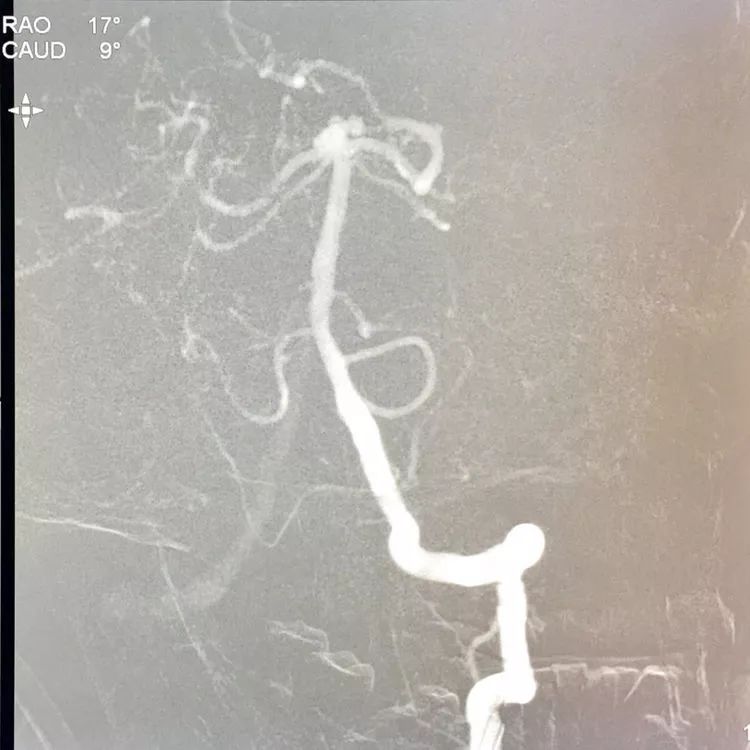

左椎动脉工作位路图